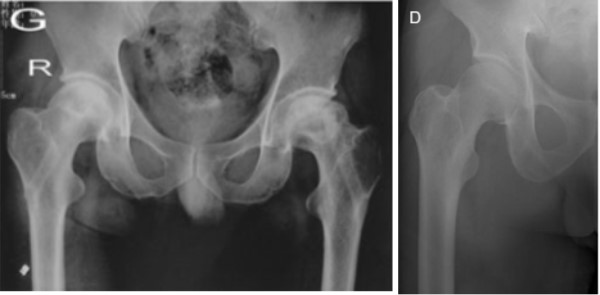

1.良好的減壓效果,有效改善血液循環(huán)

2.生物活性材料結(jié)合植骨,增強(qiáng)骨融合

3.提供足夠的力學(xué)支撐,防止股骨頭塌陷

4.無(wú)異物感和排異反應(yīng)